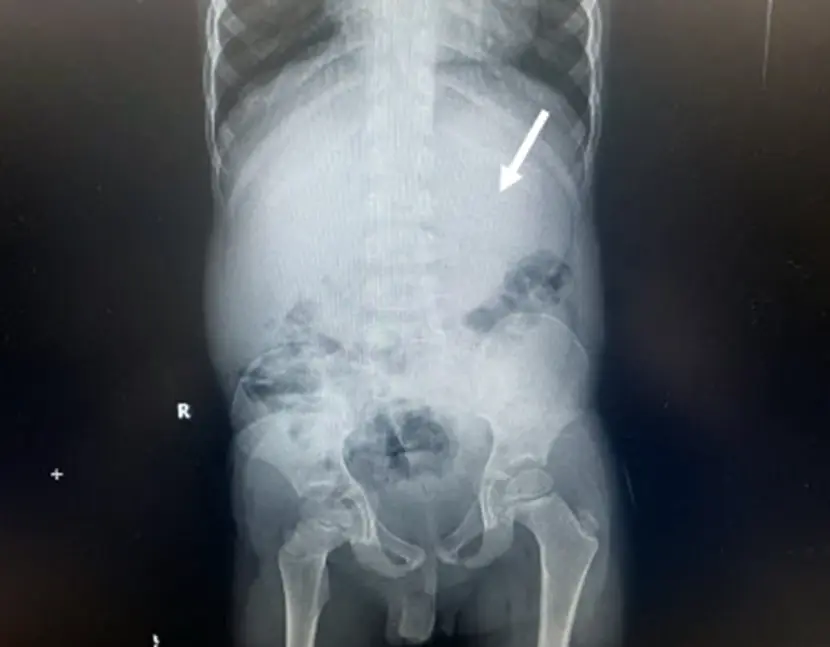

Η ομάδα των γιατρών, με επικεφαλής τον Dr. Chizite Iheonunekwu της Cleveland Clinic, ανακάλυψε το περιεχόμενο στην κοιλιά του με ακτονογραφίες, οι οποίες αποκάλυψαν τη μεγάλη μάζα.

Οι γιατροί αφαίρεσαν την τσίχλα με άκαμπτη οισοφαγοσκόπηση, με τη βοήθεια ενός μεταλλικού σωλήνα και χρησιμοποιώντας λαβίδες για να πιάσουν τη μάζα.